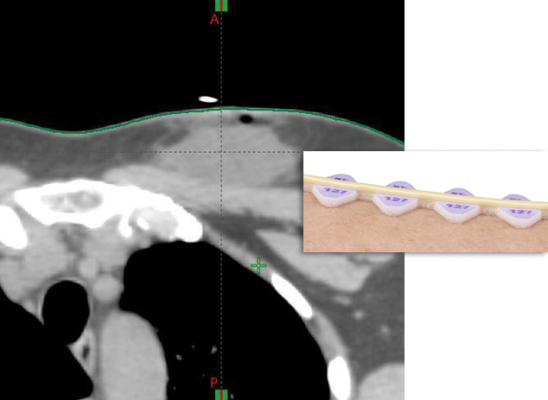

Attendees at these events specifically requested the addition of pellet and crosshair markers on the same radiolucent, elevated foam backing as the original RT-SPOT Line marker. This unique elevated design ensures that the imaging portion of the marker remains outside the automatic body contour, improving accuracy during the planning process.

Radiation therapists use multiple tools, such as immobilization devices, lasers and skin markers to ensure precise targeting of radiotherapy. However, traditional skin markers that lie flat on the skin are often included in the body outline during treatment planning, potentially leading to inaccurate dose calculations. The RT-SPOT skin markers address this issue as they are elevated from the skin line, eliminating the need for manual contouring and reducing the risk of dose inaccuracies.

According to a physicist in Northfield, Minnesota, the elevated design of RT-SPOT markers creates a clean body contour without artifacts, saving time and improving workflow efficiency for dosimetry and physicians. A dosimetrist in Bloomington, Indiana, also praised the markers for reducing the need for plan rework and enhancing overall accuracy in treatment planning.

Both the pellet and crosshair markers feature a transparent center, allowing clear visualization of the skin or thermoplastic during use.